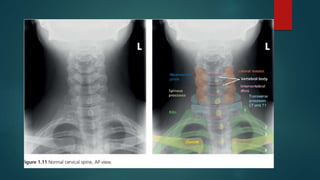

Skeletal X ray anatomy ,colour description, Imaging anatomy of musculoskeletal X rays, Diagnosis imaging anatomay, Radiology